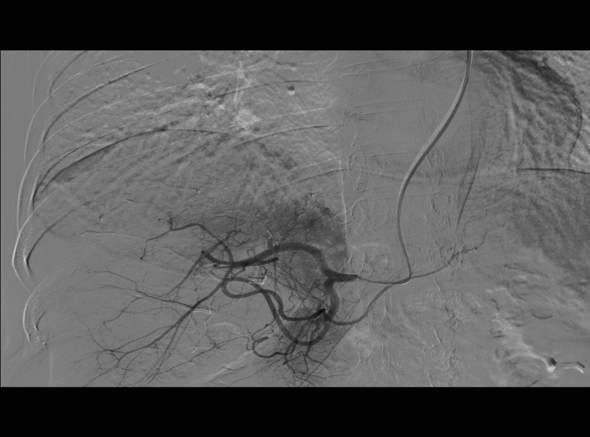

DSA(五)

检查时间:2018年10月22日

影像图谱:

供血动脉栓塞后肝固有动脉造影,栓塞满意。但未行肝总动脉造影

结果说明:

2018年10月22日行TRA-TACE术,术中造影显示病灶部分由胃右动脉供血,术中共计用碘油4ml,艾恒100mg,吡柔比星30mg。栓塞完毕后未行肝总动脉造影。